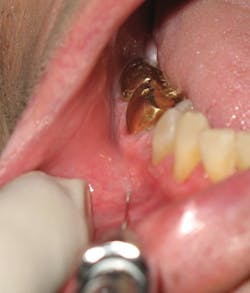

6. With the bevel oriented toward the bone, insert the needle at the depth of the mucobuccal fold usually at the canine or first premolar. Resting the syringe barrel on the finger providing retraction assists in stabilization (see Figure 5).

Figure 5: Insertion and stabilization